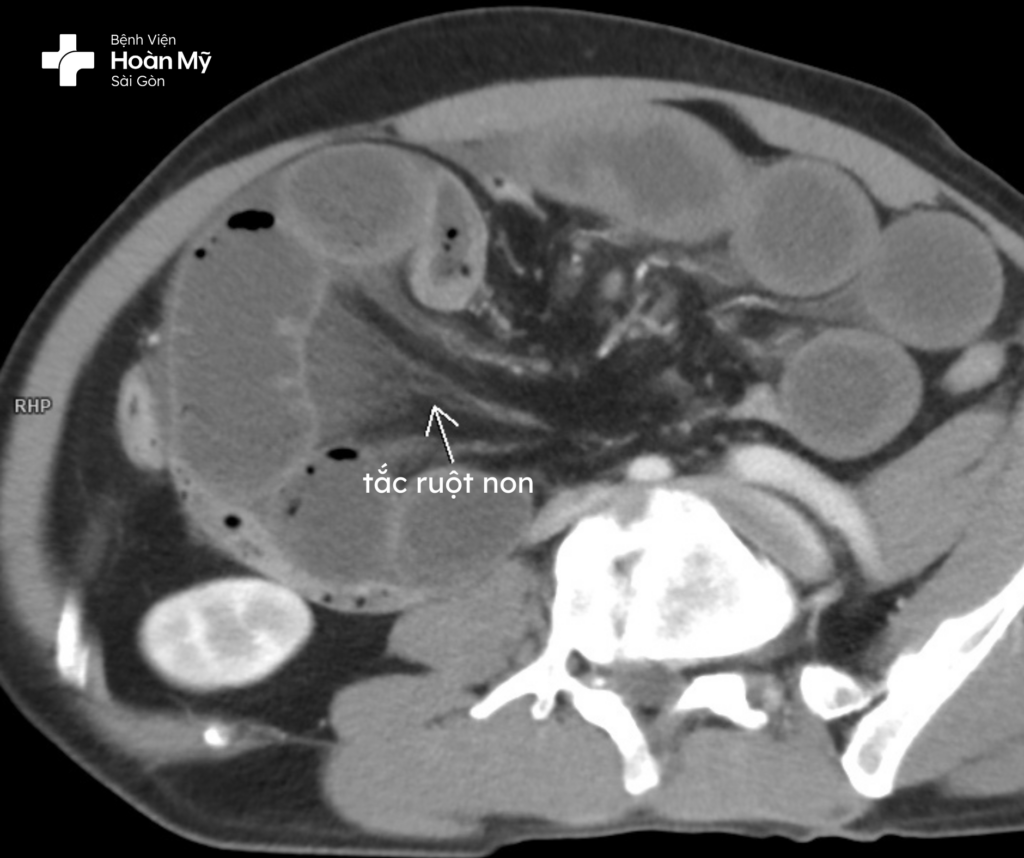

Nhận thấy tình trạng của ông C., các bác sĩ nhanh chóng hồi sức tích cực, chỉ định làm các xét nghiệm cận lâm sàng. Kết quả CT cho thấy tình trạng tắc ruột non cơ học dạng quai kín, nghi ngờ do xoắn ruột. Hình ảnh cản quang cũng cho thấy một đoạn quai ruột non bắt quang kém hơn các quai ruột còn lại, nghi ngờ có hoại tử. Chỉ số bạch cầu tăng cao (13.3 x 10⁹/L), hemoglobin giảm (còn 98 g/L), cho thấy nguy cơ nhiễm trùng và tổn thương mô vô cùng nghiêm trọng.

Kết quả CT cho thấy tình trạng tắc ruột non cơ học dạng quai kín, nghi ngờ do xoắn ruột